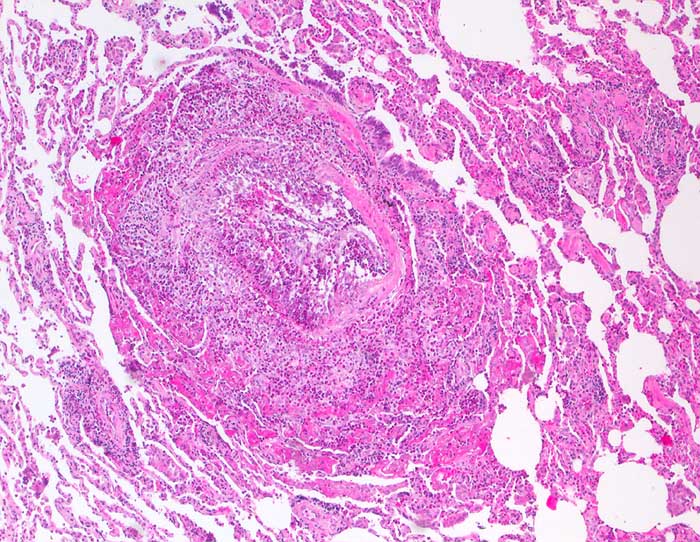

n/ Churg Strauss Vaskulitis

Churg Strauss Vaskulitis

Die zytologischen Veränderungen bei der Churg Strauss Vaskulitis entsprechen den Veränderungen bei allergischem Asthma bronchiale. Im Vordergrund steht eine massive Vermehrung eosinophiler Granulozyten. Histologisch findet sich zusätzlich eine nekrotisierende eosinophile Vaskulitis.